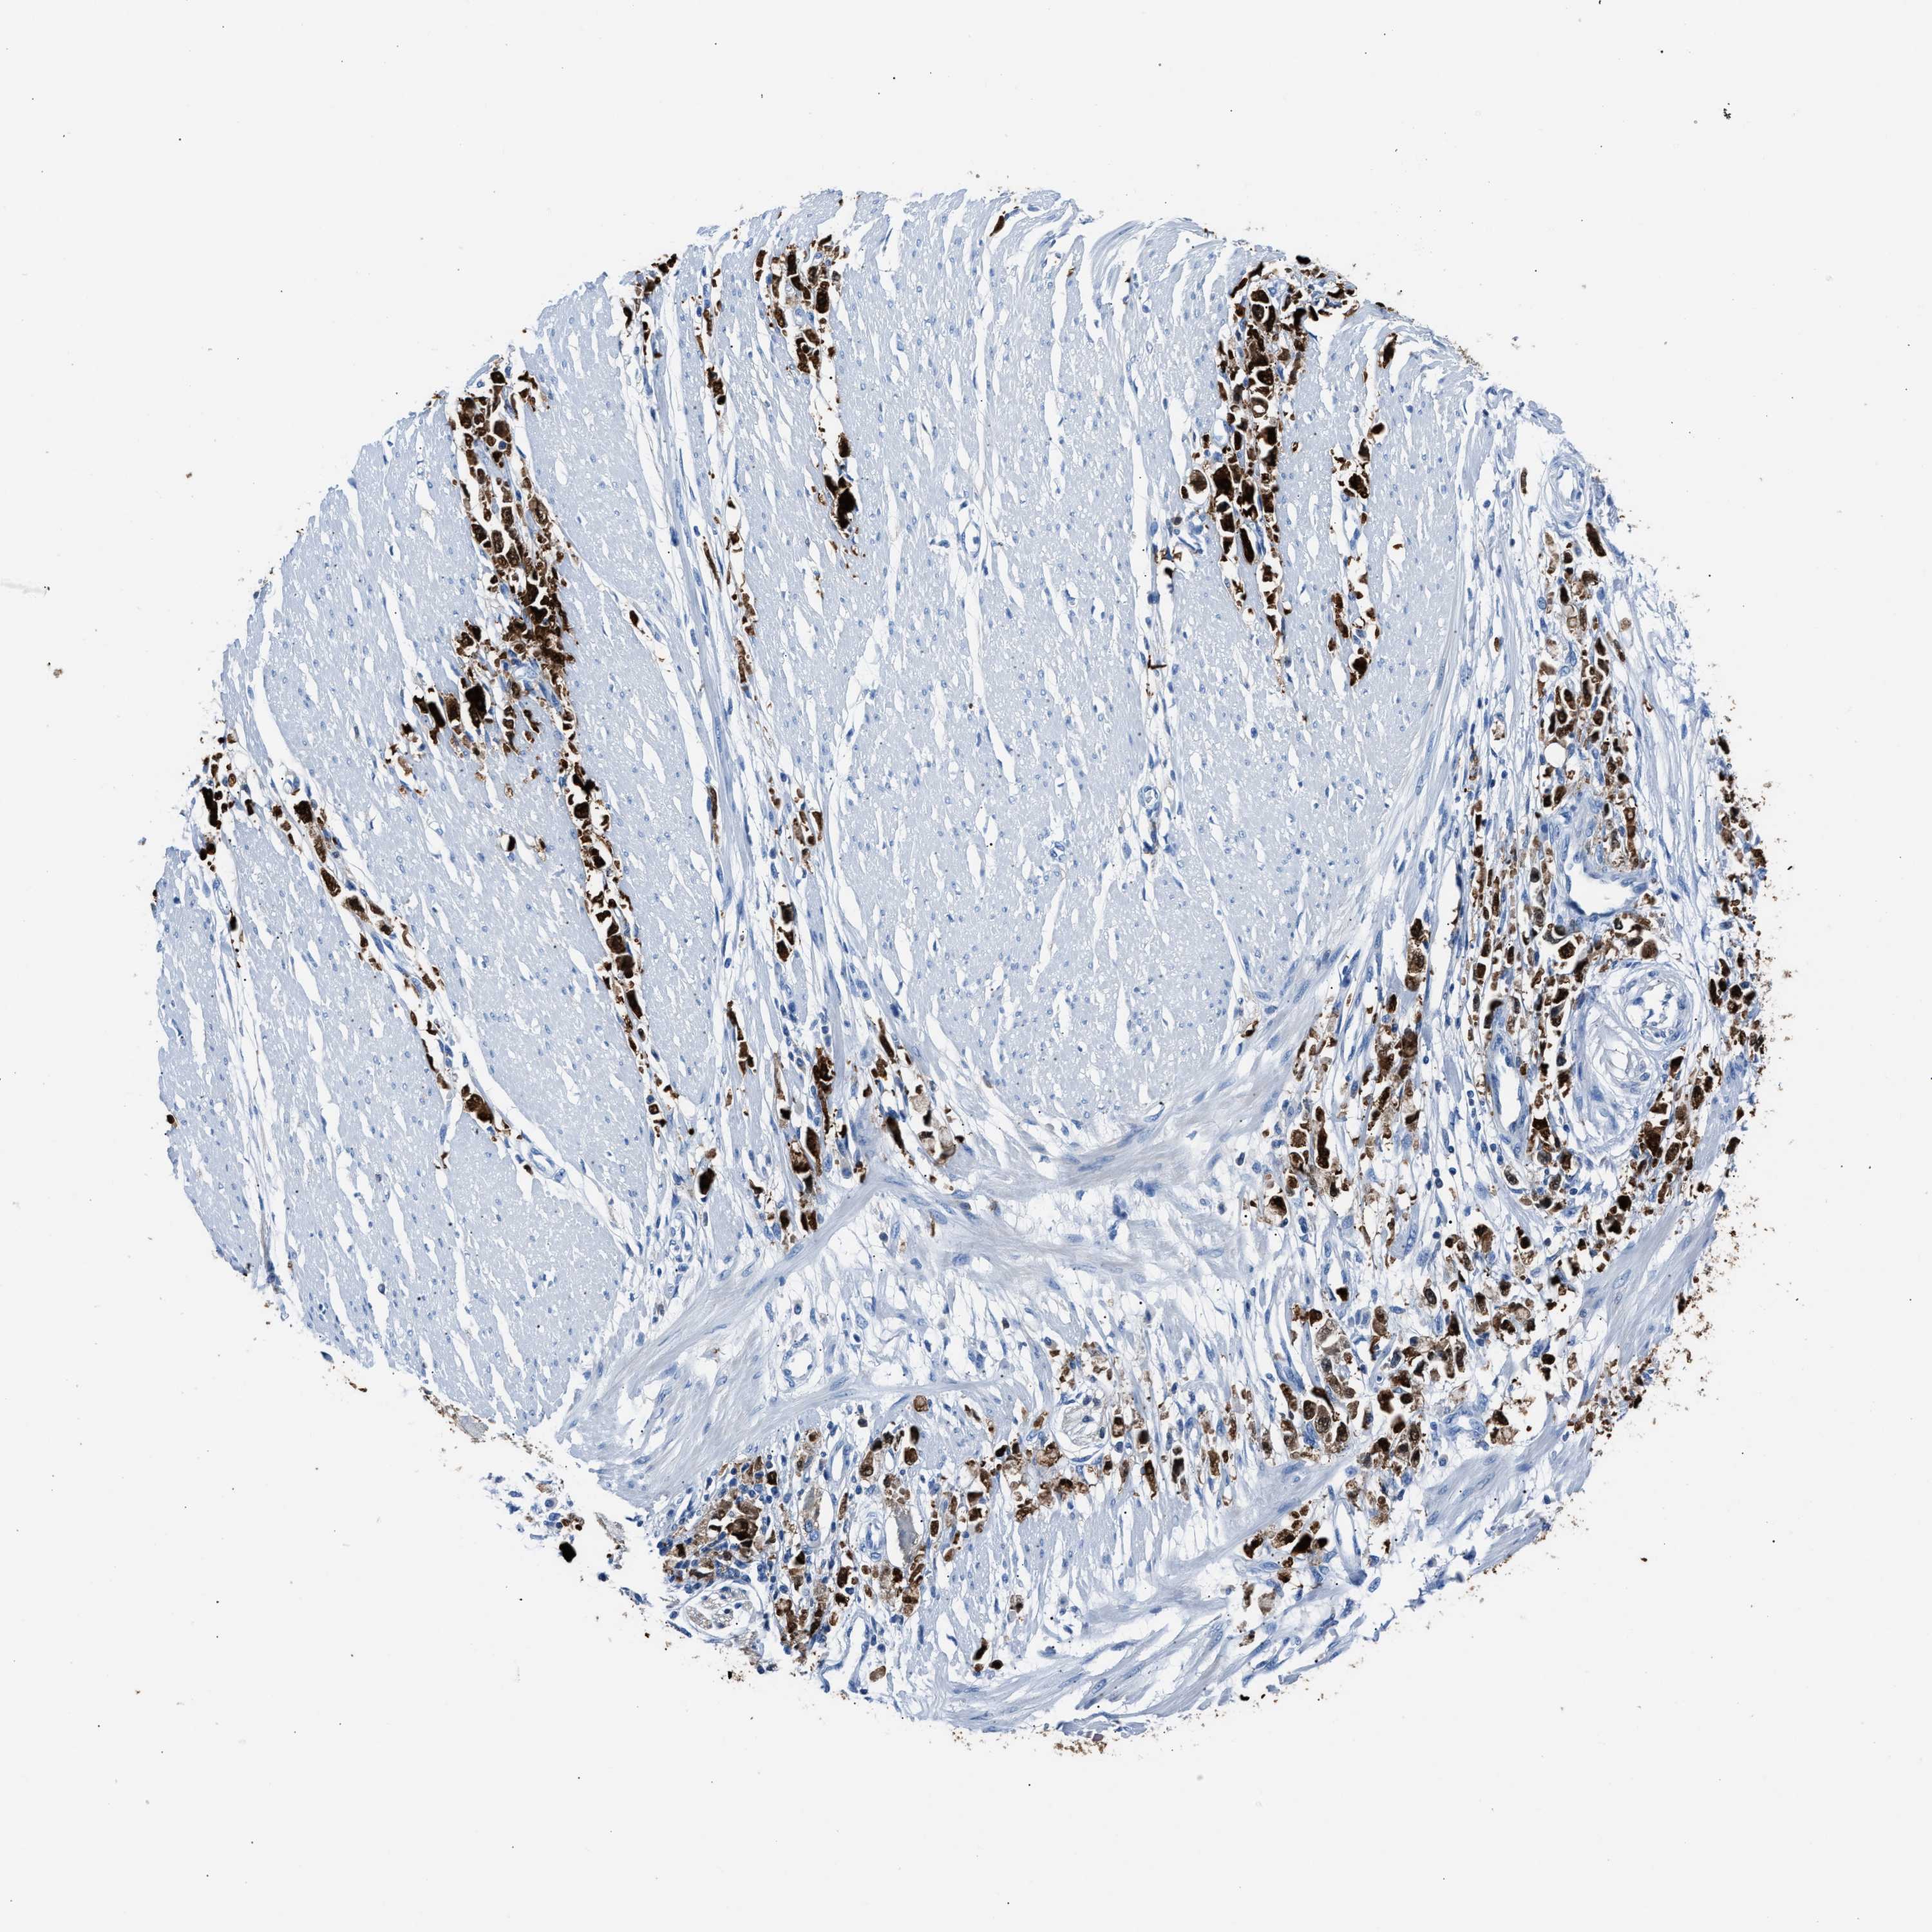

STOMACH CANCER - Protein expressioni

A mouse-over function shows sample information and annotation data. Click on an image to view it in a full screen mode. Samples can be filtered based on level of antibody staining by selecting one or several of the following categories: high, medium, low and not detected. The assay and annotation is described here.

Note that samples used for immunohistochemistry by the Human Protein Atlas do not correspond to samples in the TCGA dataset.

Antibody stainingi

Antibody staining in the annotated cell types in the current human tissue is reported as not detected, low, medium, or high, based on conventional immunohistochemistry profiling in selected tissues. This score is based on the combination of the staining intensity and fraction of stained cells.

Each image is clickable and will lead to virtual microscopy that enables deeper exploration of all samples and also displays staining intensity scores, fraction scores and subcellular localization as well as patient and tissue information for each sample.

Antibody HPA019502

Staining

High

Medium

Low

Not detected

Intensity

Strong

Moderate

Weak

Negative

Quantity

>75%

75%-25%

<25%

None

Location

Nuclear

Cytoplasmic/membranous

Cytoplasmic/membranous,nuclear

Adenocarcinoma, NOS